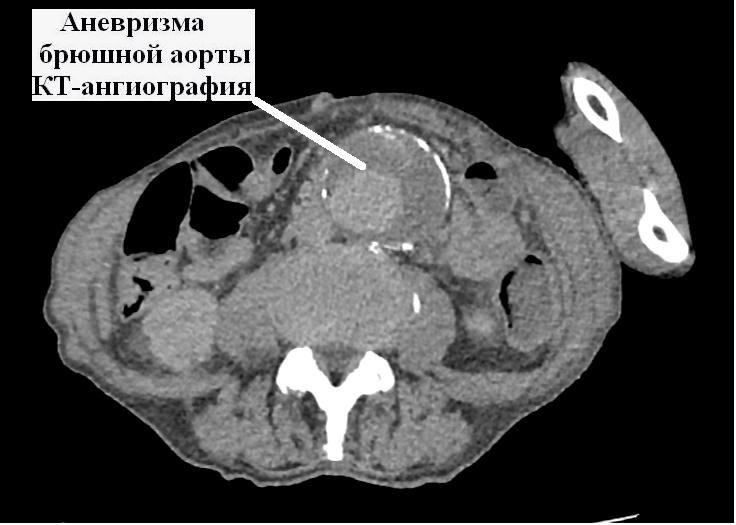

В Коломенскую больницу поступил 79-летний мужчина с выраженным болевым синдромом в животе. После проведения ультразвукового исследования, а затем компьютерной томографии с контрастным усилением врачи диагностировали аневризму брюшного отдела аорты. Патология представляет собой локальное расширение сосуда с постепенным истончением его стенки. У пациента ее диаметр превышал 10 см при нормальном диаметре аорты 18–22 мм.